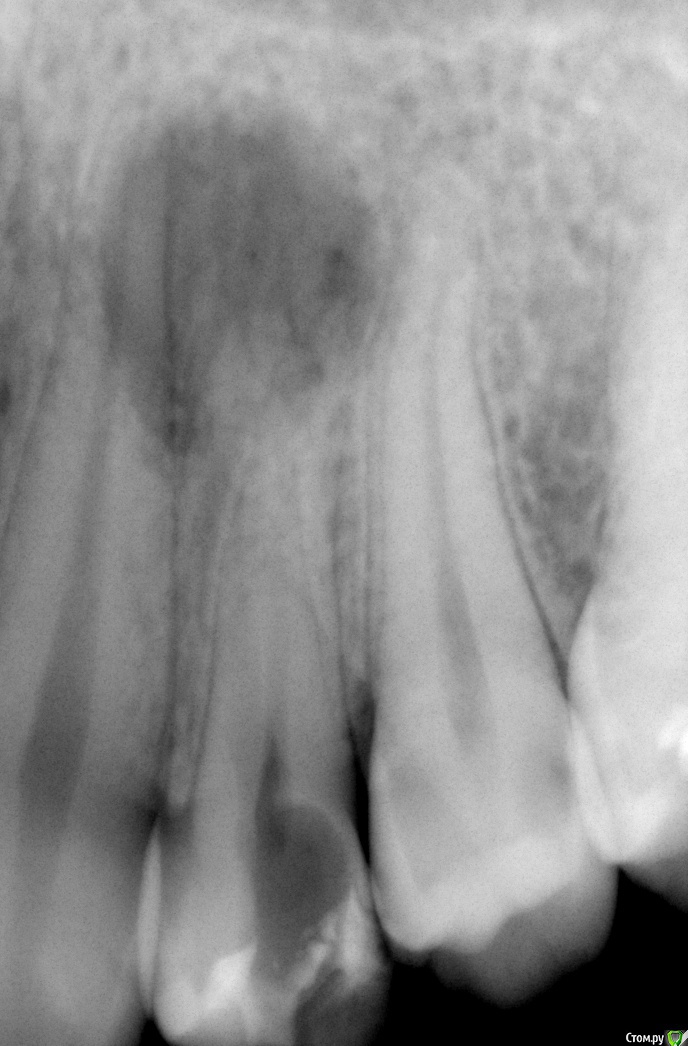

Zemtsov.alexander Опубликовано 23 октября, 2019 Автор Поделиться Опубликовано 23 октября, 2019 Спустя два месяца пациент пришёл на осмотр, есть лёгкая реакция на перкуссию. Судя по снимку есть воспаление на 45 зубе, но реагирует именно 46 Ссылка на комментарий

Zemtsov.alexander Опубликовано 23 октября, 2019 Автор Поделиться Опубликовано 23 октября, 2019 Вот панорамный снимок Ссылка на комментарий